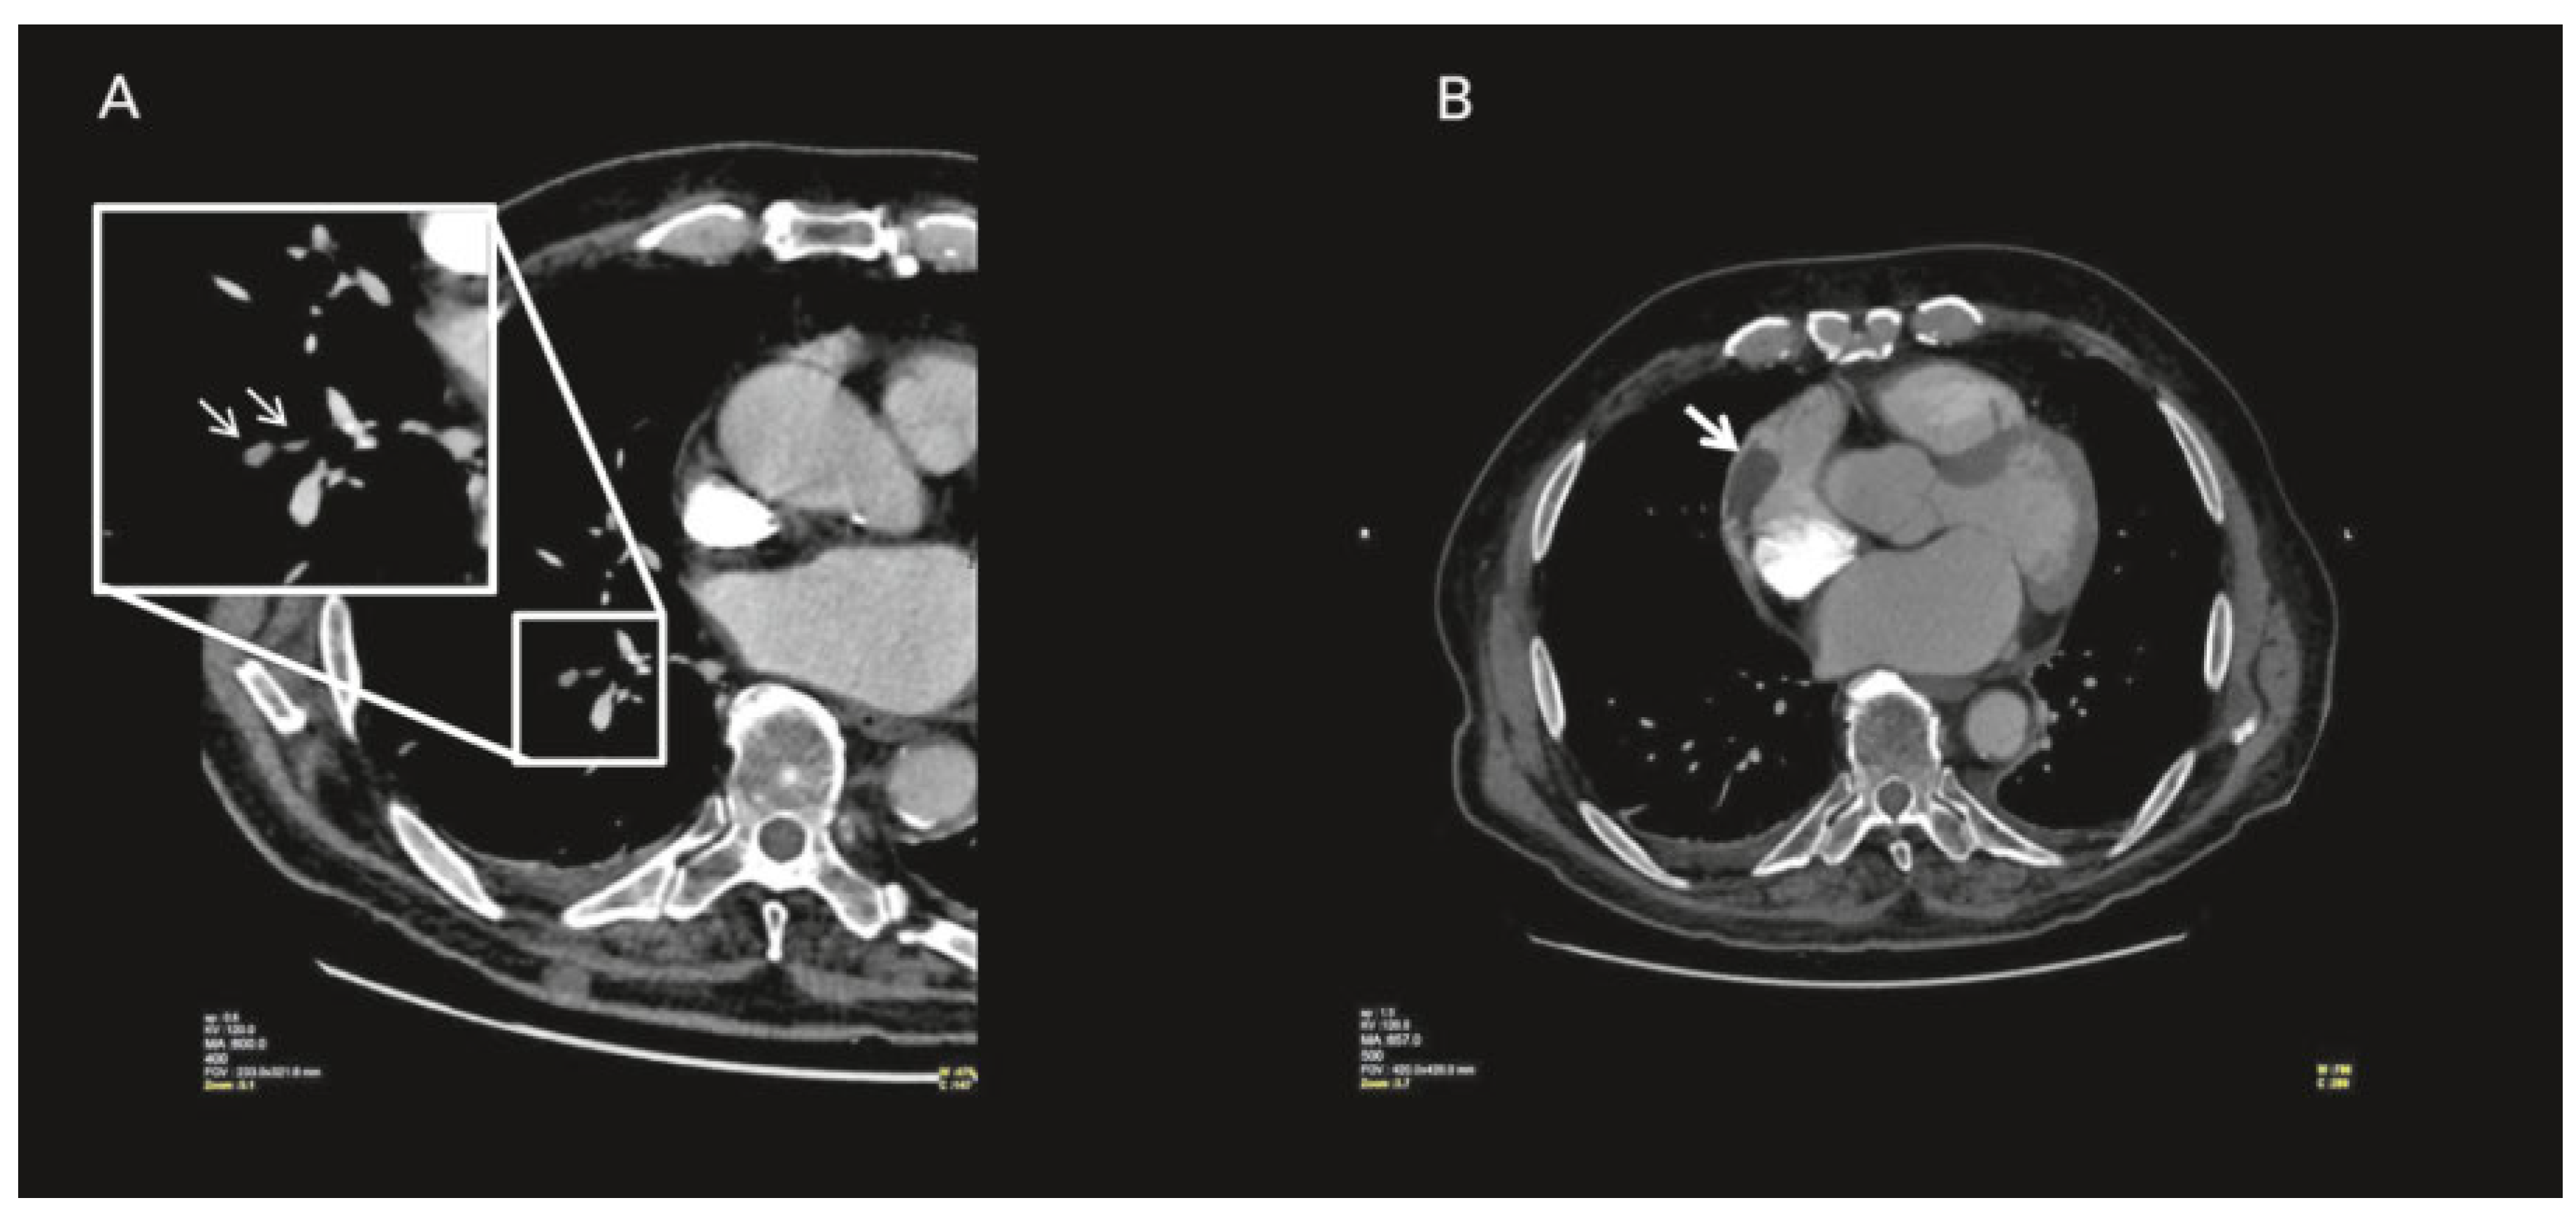

Case report